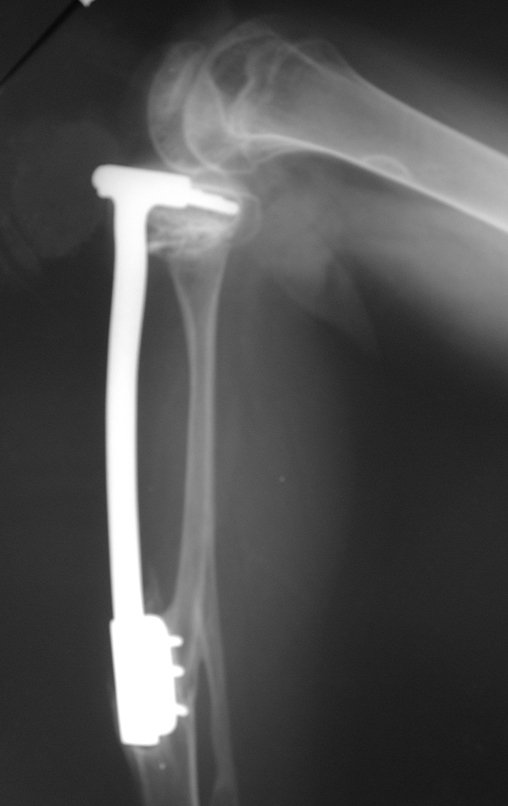

El autotrasplante del peroné vascularizado, con su placa de crecimiento, está demostrando ser una solución biológica eficaz. El peroné se “tibializa” y su placa de crecimiento continúa creciendo, reemplazando la placa de crecimiento tibial, que fue resecada junto con el tumor.

Miembro inferior alineado y clínicamente con la pierna más corta, ya que el acortamiento se produjo desde el inicio, debido a la inclinación de la epífisis, provocando deslizamiento inferior del vástago de la placa, ya demostrado con la inclinación de los tornillos epifisarios.

Véase el artículo sobre este dispositivo de fijación interna extensible que desarrollamos, así como el uso de esta técnica en los dos primeros casos, publicado en la Revista Brasileira de Ortopedia – Vol. 36, nº 7 – julio de 2001, Figura. 166. Se puede acceder y descargar este artículo completo en PDF directamente desde el siguiente enlace: